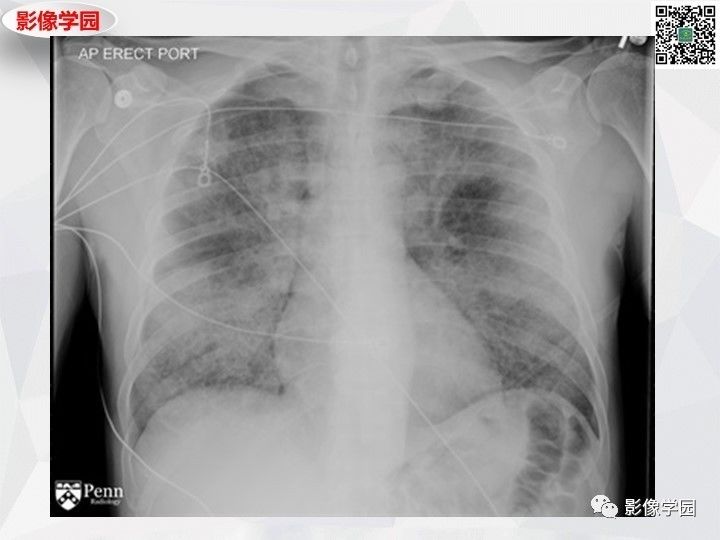

Findings

Diagnosis: Pulmonary alveolar proteinosis

The patient underwent bronchoalveolar lavage, which demonstrated milky and turbid fluid with thick sediment. Cytology demonstrated large foamy macrophages. Serum antigranulocyte-macrophage colony-stimulating factor (anti-GM-CSF) autoantibodies were positive.